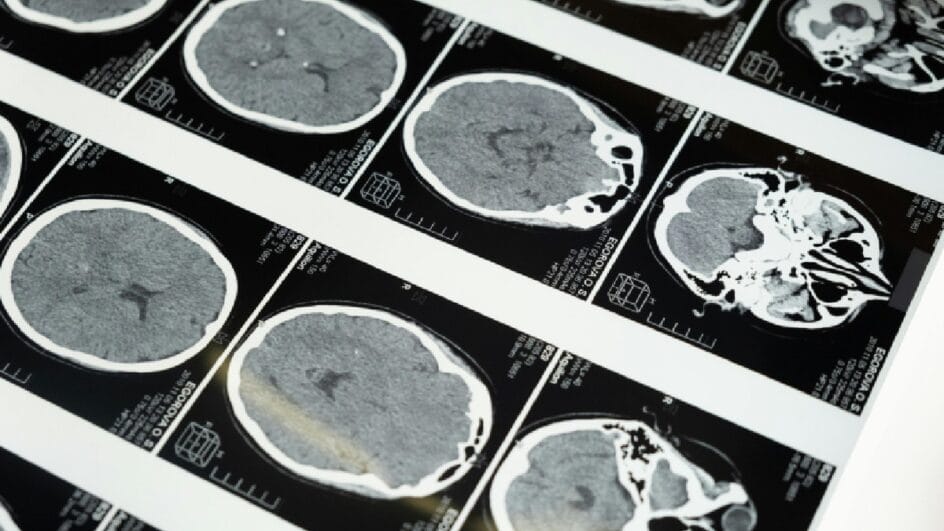

É o que indica um novo estudo realizado por pesquisadores noruegueses e publicado na revista Proceedings of the National Academy of Sciences (PNAS). O estudo é um dos mais completos do gênero, com mais de 12 mil exames de ressonância de quase 5 mil pacientes.

A velhice traz vários efeitos indesejáveis para o corpo humano. Um deles é a perda de massa cinzenta de diversas regiões do cérebro. A pesquisa mostrou que, com o passar dos anos, o cérebro dos homens encolhe mais rapidamente que o das mulheres, inclusive nas regiões associadas ao Alzheimer.

E é uma diferença significativa: enquanto os cérebros das mulheres analisados apresentaram 1,2% de perda por ano, os dos homens chegavam a 2% por ano. Os pesquisadores esperavam que a diferença de velocidade explicasse a proeminência do Alzheimer, mas o resultado foi o oposto.